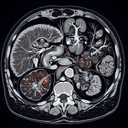

МРТ підшлункової залози

МРТ підшлункової залози — це неінвазивний метод дослідження, який дозволяє отримати детальну інформацію про стан підшлункової залози та прилеглих структур. Ця процедура є безболісною і використовує магнітне поле та радіохвилі для створення детальних зображень органа. ### Переваги МРТ: - **Висока якість зображень:** МРТ надає детальні зображення, що допомагає виявити навіть незначні патології...